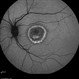

- Fundus autofluorescence imaging of a patient with autosomal recessive Best disease